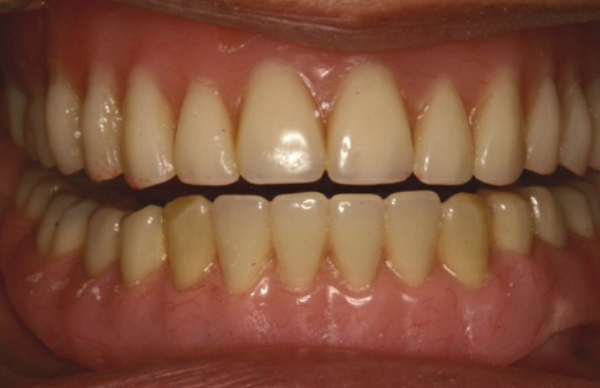

配合扣環式人工植牙

銀髮族植牙

植牙與活動假牙結合,活動假牙可以穩定咀嚼不會脫落。